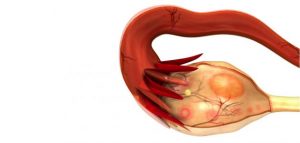

- تكيس المبايض :

تعتبر مشكلة تكيس المبايض أحد أكثر الأسباب شيوعًا وراء ألم المبيض الأيسر، والتي تحدث نتيجة تراكم حويصلات شبيهة بالأكياس حول المبيض، وغالبًا ما تتكون خلال عملية الإباضة وبعد الولادة.

وعادة لا تسبب مشكلة تكيس المبايض أي أعراض وتختفي من تلقاء نفسها، ولكن في بعض الحالات تسبب ألم شديد في المبيض إذا كان الكيس كبيرًا أو تعرض للانفجار، وفي هذه الحالة تظهر أعراض مثل “عدم انتظام الدورة الشهرية، الغثيان والقيء، ألم أثناء الجماع، انتفاخ البطن، والشعور بالشبع بعد تناول كمية صغيرة من الطعام”.

وحين تظهر أعراض تكيس المبياض تحتاج إلى تدخل للعلاج الفوري وعدم الإهمال، حتى لا ينتج عنها مشاكل صحية أخرى مثل زيادة الوزن والعقم.